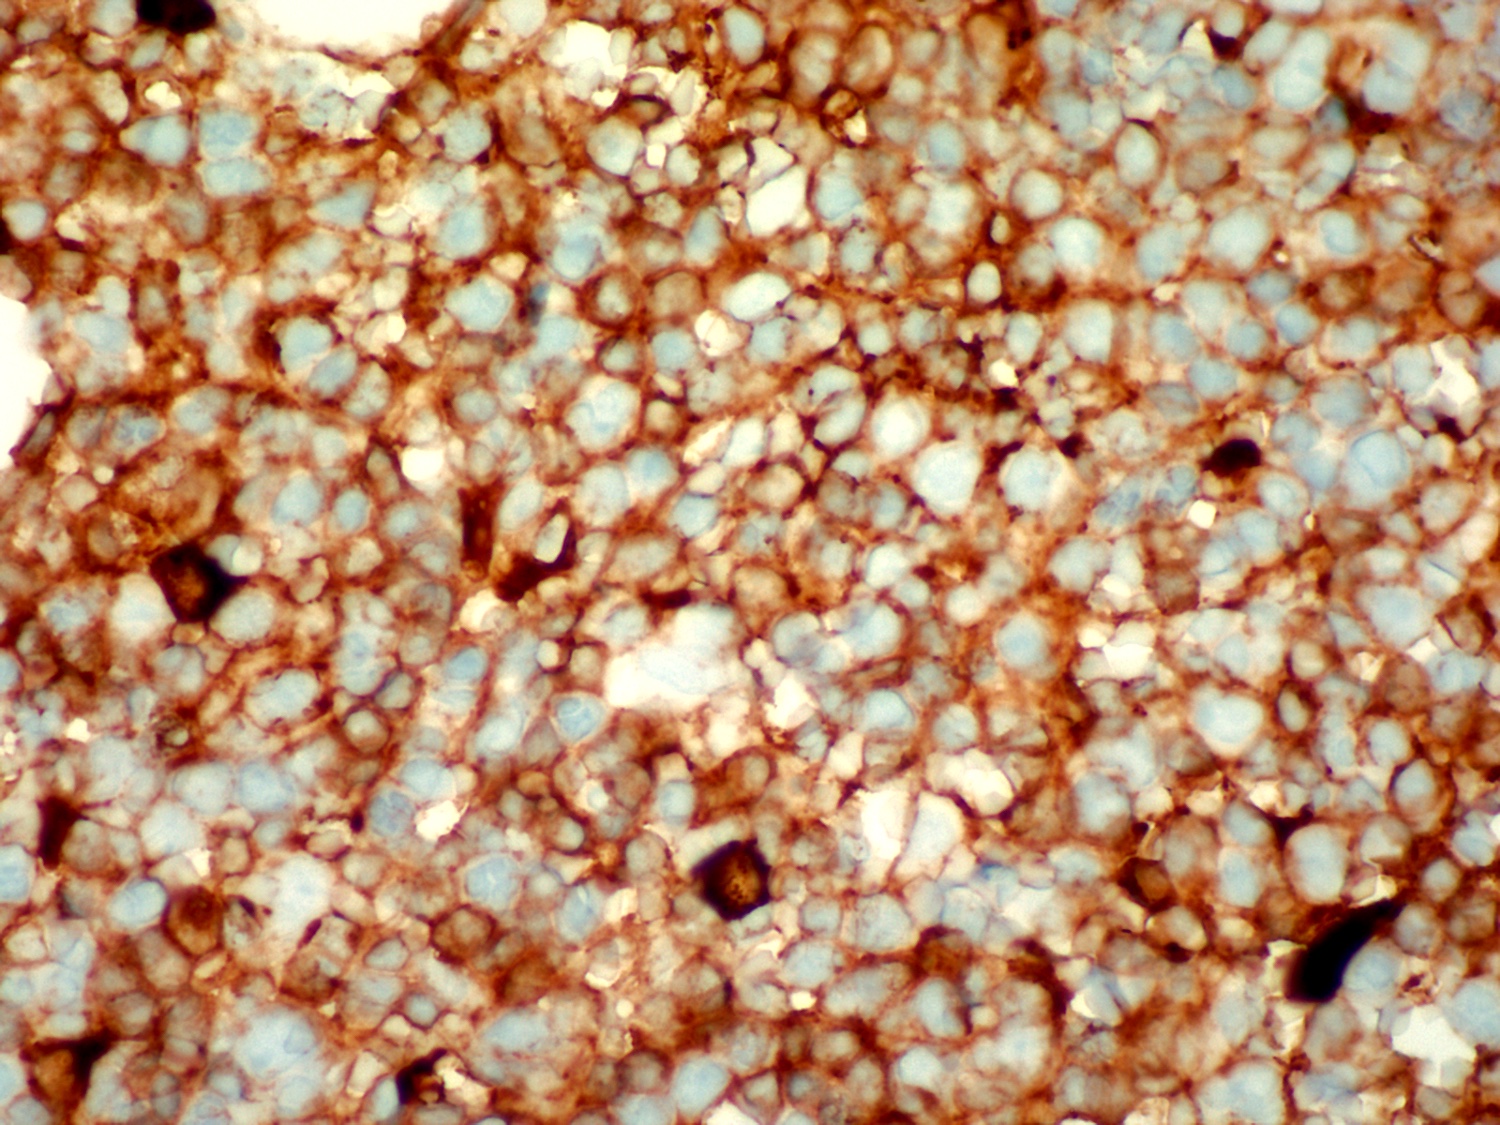

Microscopic (histologic) images

Contributed by Ling Zhang, M.D.

Positive stains